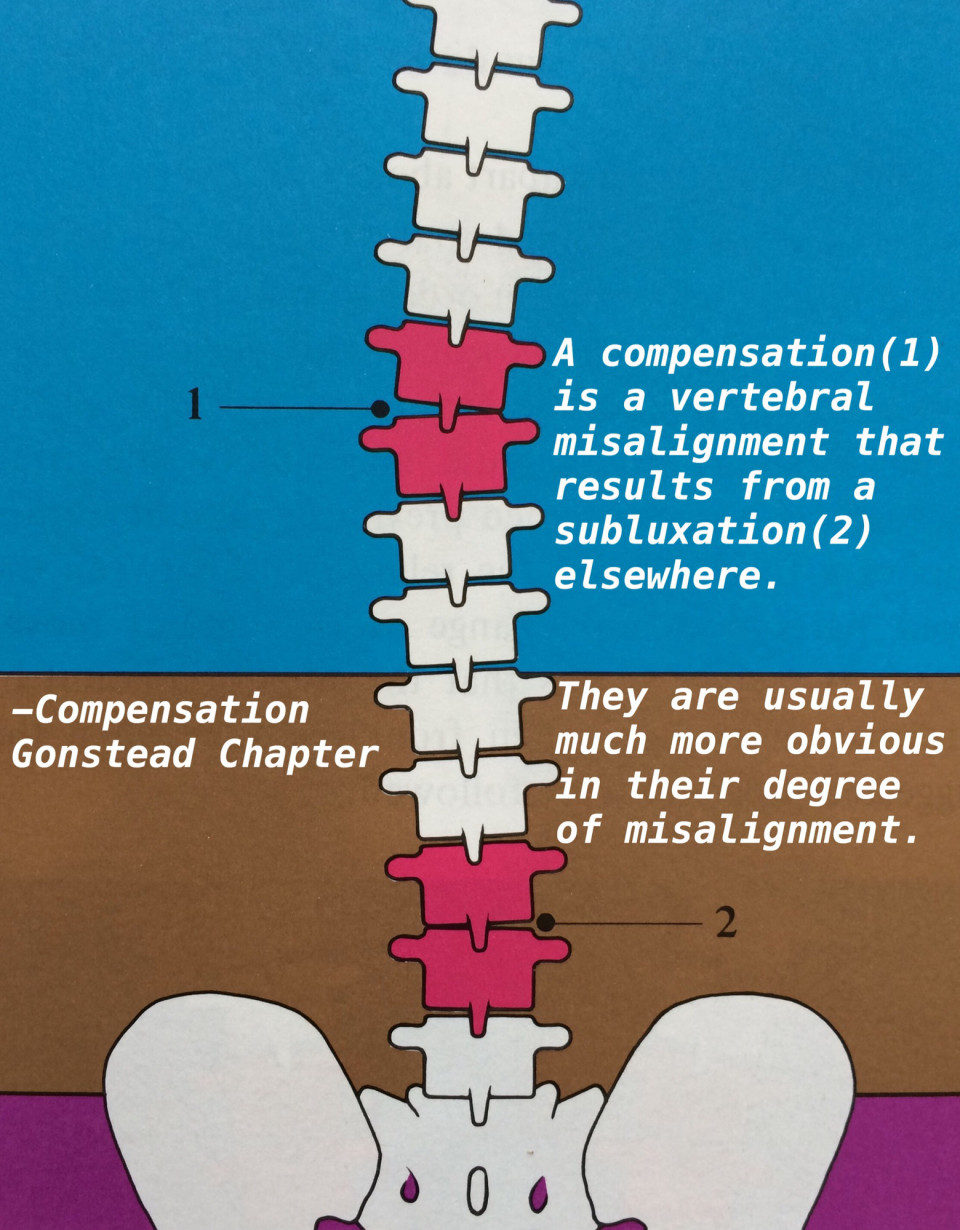

Compensation

Compensation

1番悪そうに見えても、そうとは限らない

1番悪そうに見えても、そうとは限らない